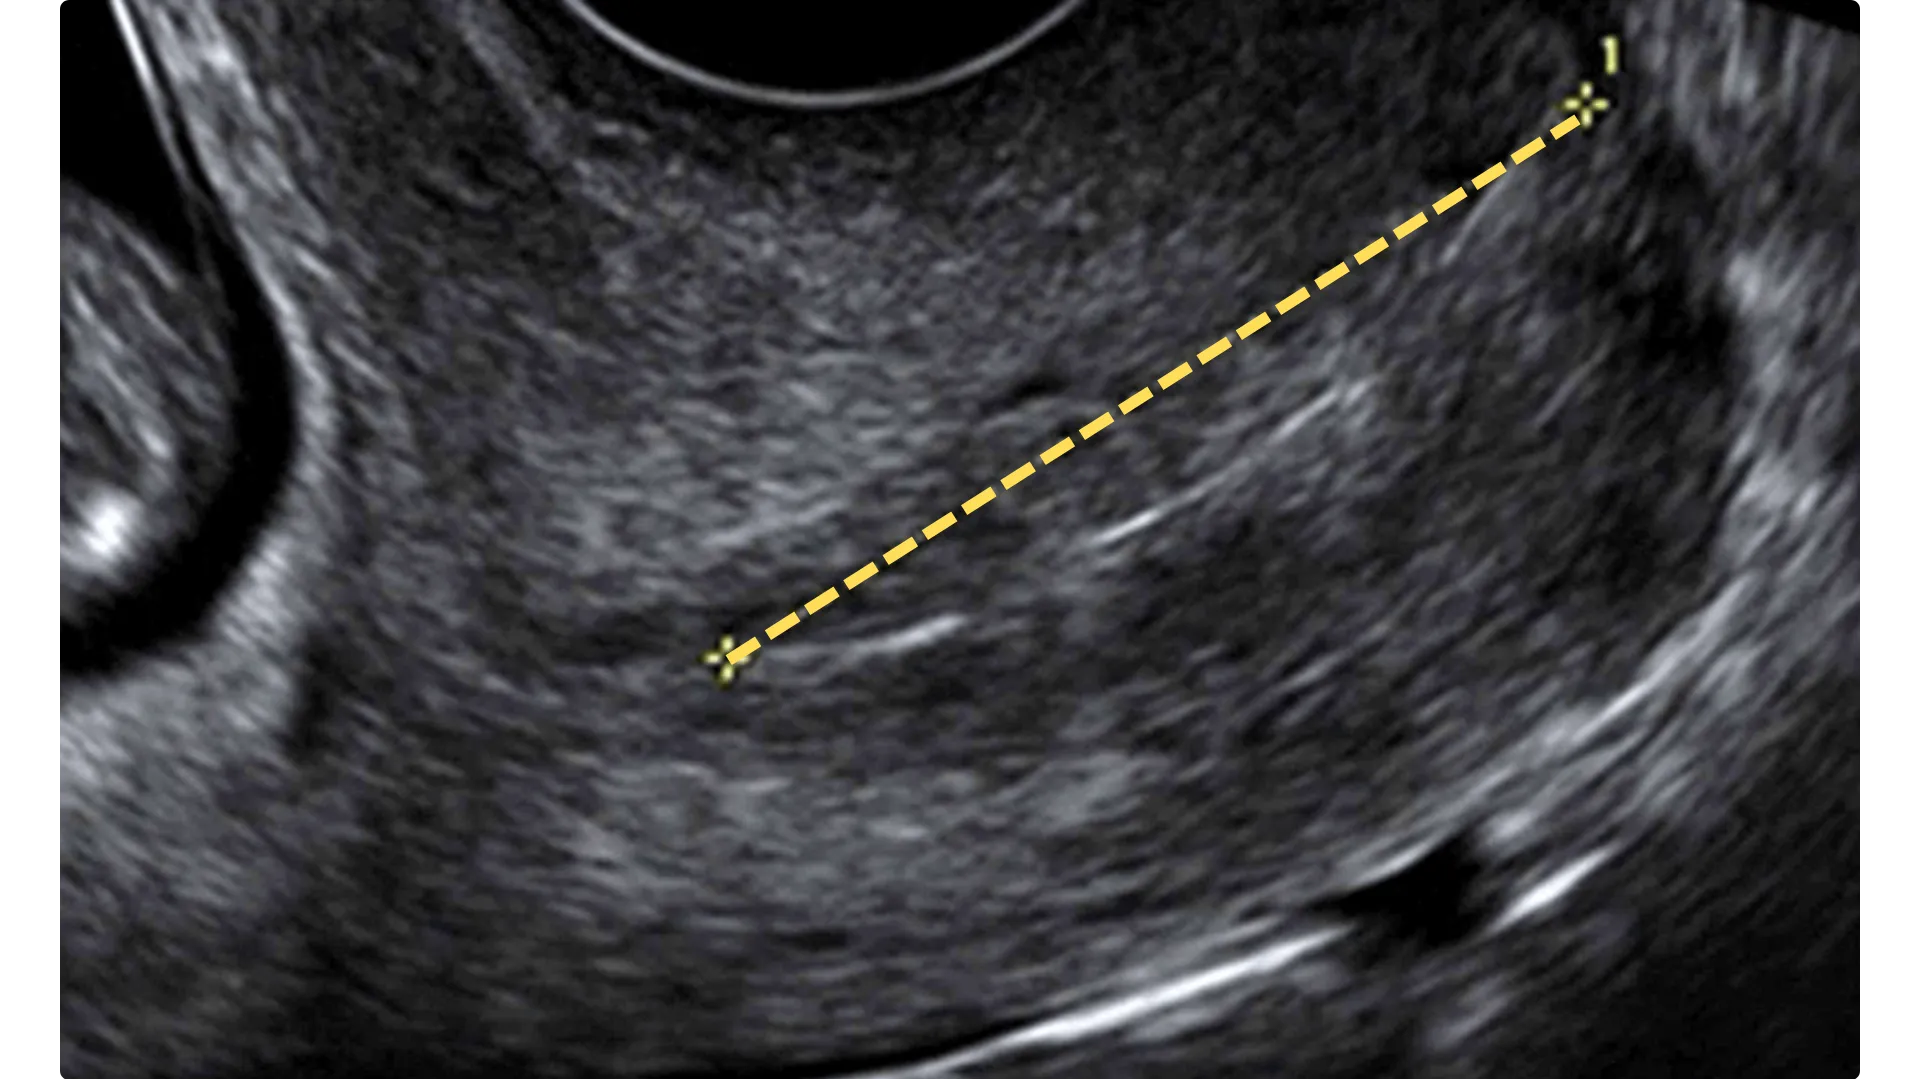

Cervicomentria

Nell’ambito nell’ecografia del 2° trimestre viene eseguita anche la cervicometria (per via transvaginale) per valutare la presenza di eventuali modificazioni della cervice (collo dell’utero) al fine di escludere il rischio di parto pretermine.

I valori normali sono 35-40 mm.

Si considera a rischio di parto pretermine una misurazione < 25 mm nelle gravidanze singole.